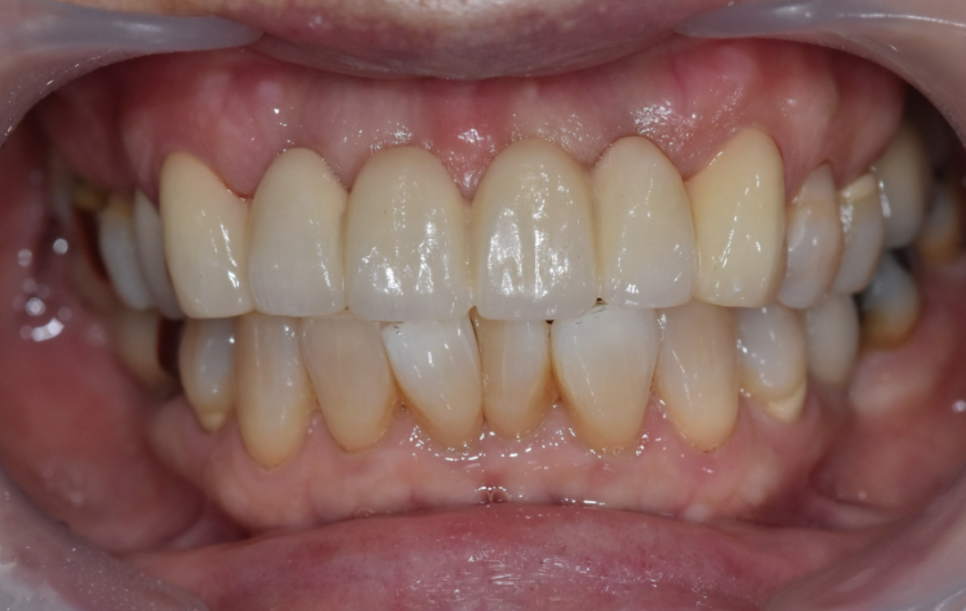

그렇게 완성된 최종 브릿지.

240719

옆 치아와의 색도 자연스럽게 나왔고,

모양과 크기도 적절했습니다.

무엇보다 환자분께서 정말 마음에 들어 하셨어요.